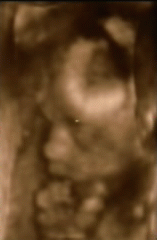

A második képen nyitva van a szeme is